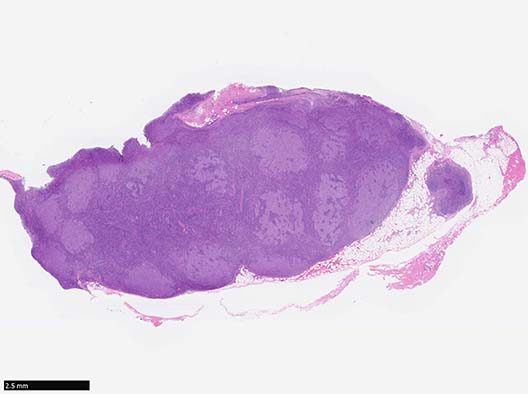

Case presentation---cervical lymph node

2年前, 頸部の腫れに気づく. 他院の生検で悪性リンパ腫(病理診断は, DLBCL)と診断される.治療目的に当院血液内科を紹介され入院. 口蓋扁桃, 上内深頸, 鎖骨上窩, 腋窩リンパ節に病変あり. R-CHOP6コースにより寛解.

頸部リンパ節: Virtual Slide--->Virtual slideをみる. sorry you need ID & psswrd to see the VS.

Follicles with "Floral pattern"

大型類円形の細胞が明るい濾胞胚中心様の構造を形成している. この濾胞構造には周囲mantle zoneより小型のリンパ球が進入して,

うねった胚中心は, 断裂した花弁様の「floral pattern」を示す.

Floral variant of follicular lymphoma

Floral variant of follicular lymphomaはマントル層の小リンパ球が腫瘍性濾胞の胚中心に侵入し濾胞が花弁状に断裂して見える濾胞性リンパ腫のまれな亜型である.*1 *2

Floral variant of FLの2つの組織学的 subtype.*2

1) Macrogerminal center pattern: mantle zone lymphocytesが濾胞に侵入し花弁状の濾胞構造を示すタイプ 70% (9/13cases)

2) Microgerminal center pattern: mantle zone lymphocytesの大量の浸潤により腫瘍性濾胞はほぼ完全に破壊されている. 30% (4/13cases)

3) 3/13casesはmarginal zone componentが含まれている.